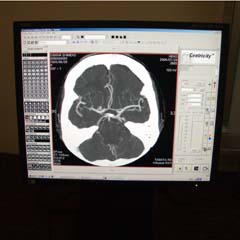

当院のCT検診は・・・

1部位5分ほどの簡単な検査です。放射線被曝にも配慮しながら検査を行っています。又検査には、最新型マルチスライスヘリカルCTを使用し、精度も臨床の精密検査と同等です。

検査直後、画像診断の専門医が検査画像を示し、ていねいに説明します。